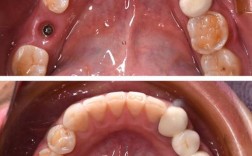

舌侧矫治器:

(图片来源网络,侵删)- 原理: 将托槽和弓丝粘在牙齿的内侧(舌侧)。